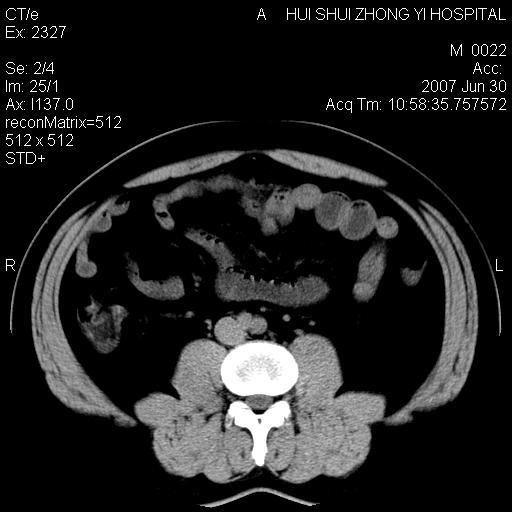

双肾结石

双侧肾盂、输尿管内结石,双侧肾脏轮廓呈波浪状,可能以前有过感染的

支持双肾结石

双肾结石.

双侧肾盂结石。

双肾结石,做个b超结合看一下。

病人呼吸动了,第四层应该在第五\\六层之间。肝右叶低密度影为胆囊部分容积效应。双肾结石。

双肾结石,少量腹腔水?

支持双肾结石。与患人呼吸有关。布分容积效应。

支持双肾结石,肝右叶低密度影为胆囊部分容积效应。